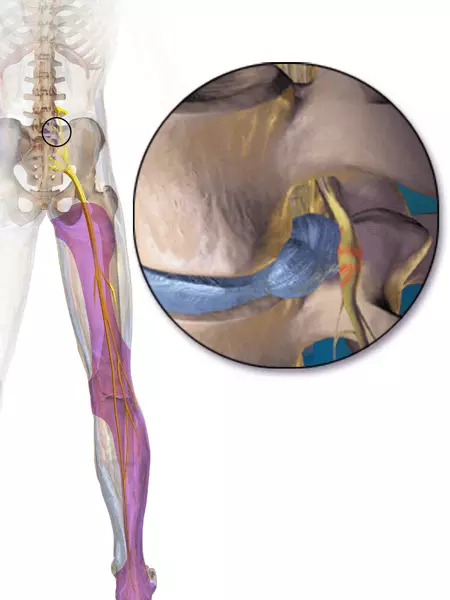

Sciatica is pain/paraesthesia caused by compression of the sciatic nerve or by one or more of the contributing spinal nerves (L4-S3). It presents with pain in the lower back and buttocks that radiates to one or more of the following dermatomes:

- L4: Anterior thigh and knee, and medial leg

- L5: Lateral thigh and leg, and dorsum of the foot

- S1: Posterior thigh and leg, and sole of the foot

Sciatica usually self resolves within 4-6 weeks. If symptoms are severe or persistent, the GP may suggest exercises and stretches, prescribe additional painkillers and refer to physiotherapy.

Image - The distribution of pain/paraesthesia in sciatica

Creative commons source by BruceBlaus [CC BY-SA 4.0 (https://creativecommons.org/licenses/by-sa/4.0)]